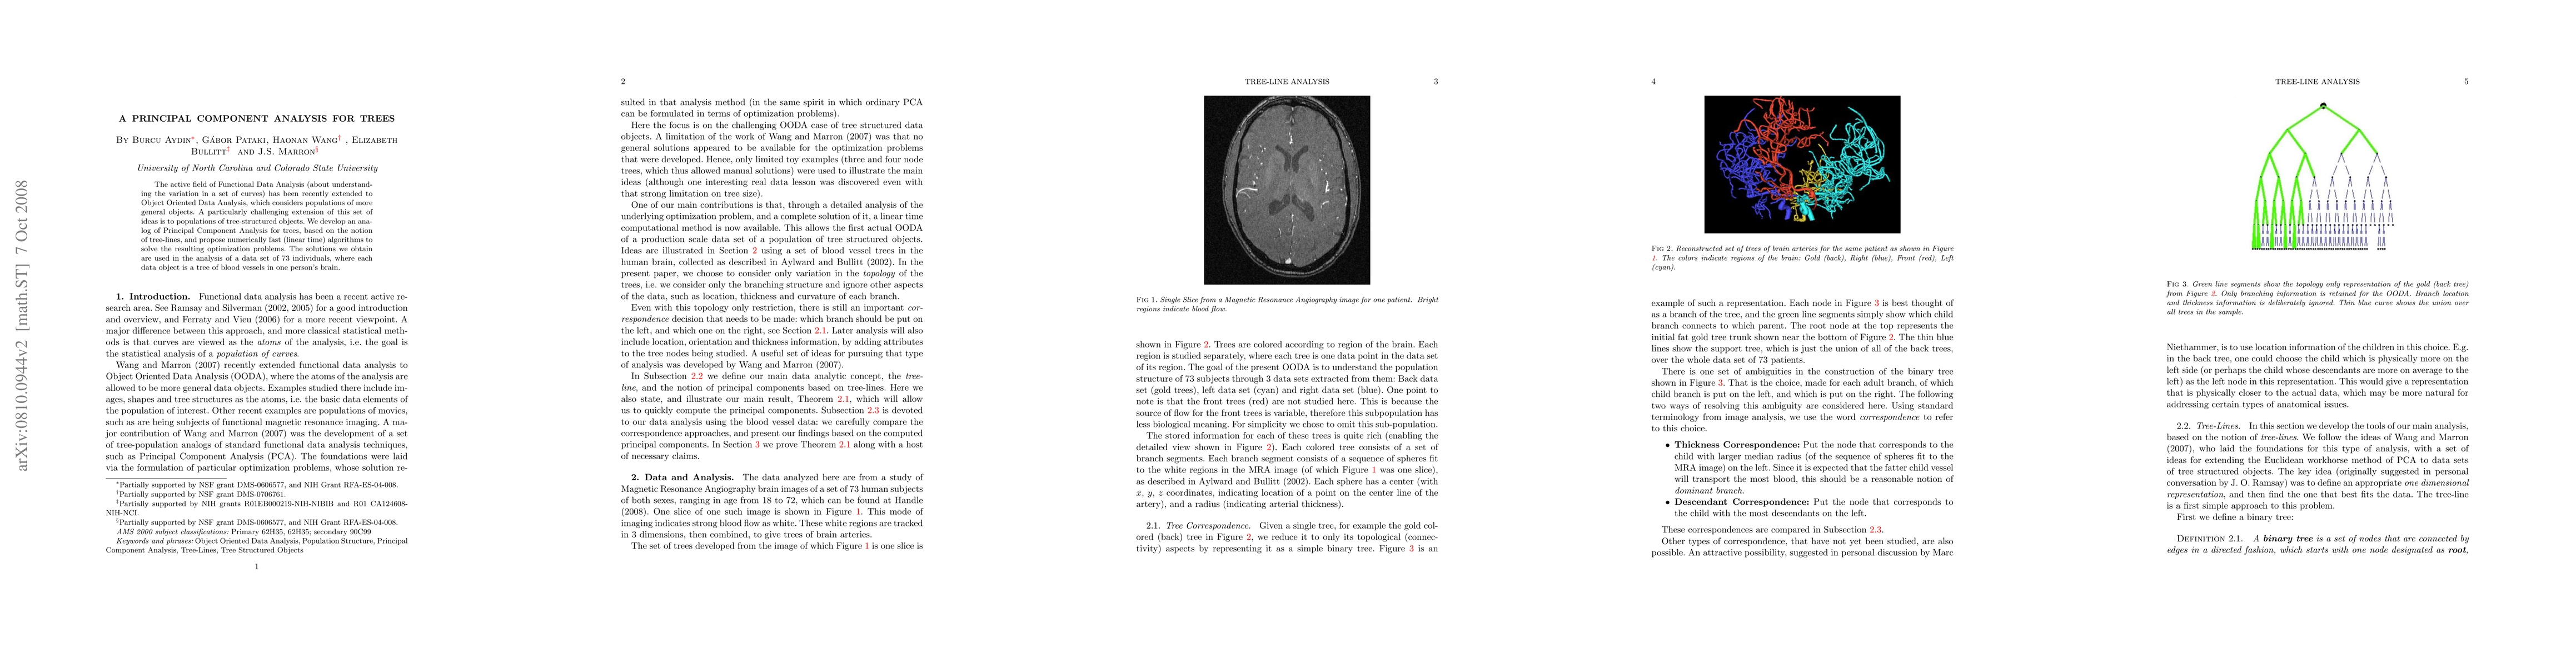

The active field of Functional Data Analysis (about understanding the variation in a set of curves) has been recently extended to Object Oriented Data Analysis, which considers populations of more general objects. A particularly challenging extension of this set of ideas is to populations of tree-structured objects. We develop an analog of Principal Component Analysis for trees, based on the notion of tree-lines, and propose numerically fast (linear time) algorithms to solve the resulting optimization problems. The solutions we obtain are used in the analysis of a data set of 73 individuals, where each data object is a tree of blood vessels in one person's brain.